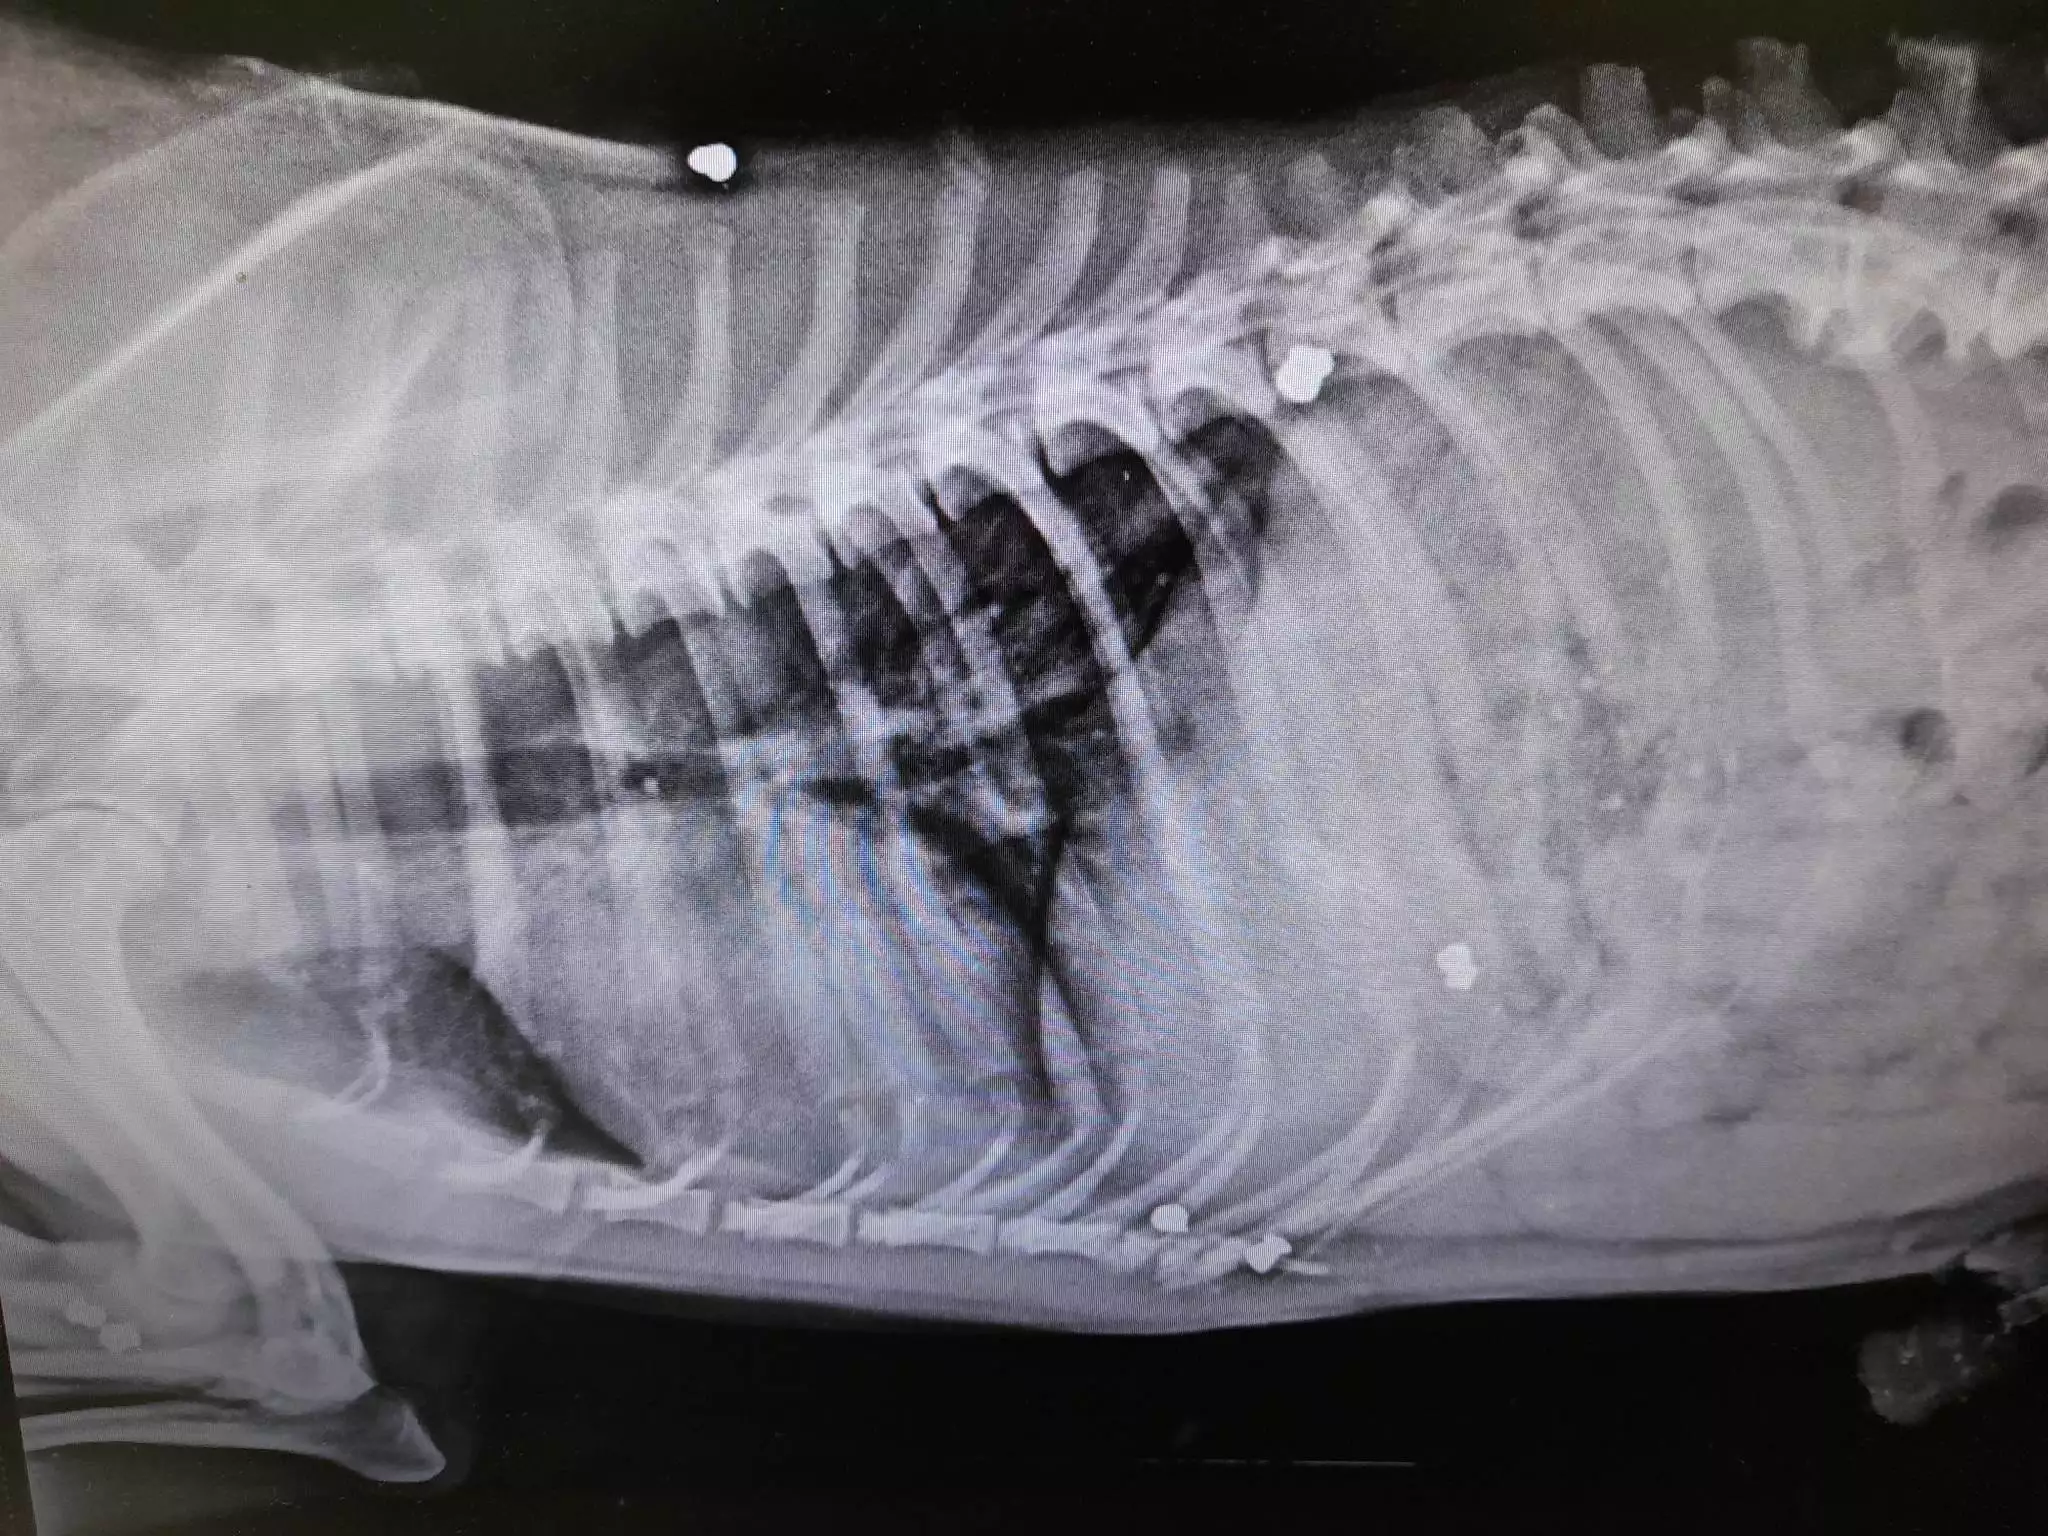

- Όλα έγιναν το πρωί της Δευτέρας 20 Μαρτίου του 2023 στο Ψυχικό στις Σέρρες. Όπως αναφέρει σε ανάρτησή του ο Φιλοζωικός Σύλλογος Εμμανουήλ Παππά, ο αδέσποτος σκύλος Smiley, δέχθηκε τουλάχιστον 10 πυροβολισμούς από αεροβόλο όπλο που κρατούσε στα χέρια του ασυνείδητος κάτοικος του χωριού, με αποτέλεσμα να βρει φρικτό θάνατο.

Μάλιστα, το άψυχο σώμα του σκύλου εντοπίστηκε πεταμένο στα σκουπίδια. Ο νεκρός σκύλος μεταφέρθηκε σε κτηνιατρείο αλλά παρά τις προσπάθειες που έγιναν δεν επανήλθε στη ζωή. Η κοινωνία στις Σέρρες, παραμένει ανάστατη από τα όσα έγιναν, με τους αστυνομικούς να προσπαθούν να φτάσουν στα ίχνη του δράστη, μέσα από μαρτυρίες αλλά και οι εικόνες που κατέγραψαν οι κάμερες ασφαλείας της περιοχής.